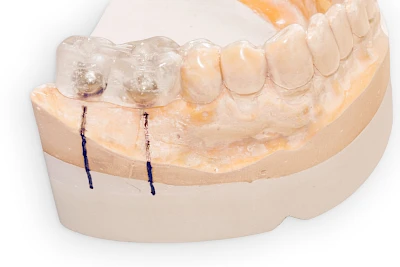

In diesen Fällen kann die Planung mittels verschieden aufwendiger Röntgen-Techniken (Übersichtsaufnahme, DVT) ggf. unter Zuhilfenahme speziell angefertigter Planungsschablonen sinnvoll sein.